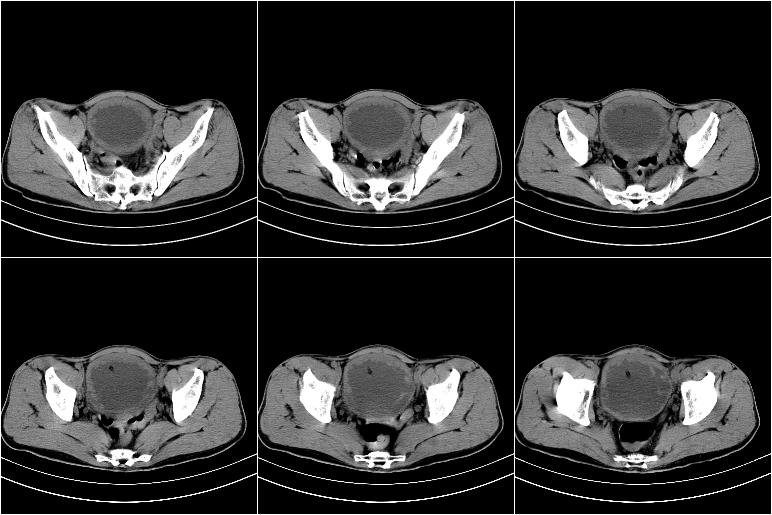

标题: CT21568:男,57岁,双肾及输尿管重度积水。彩超示前列腺占 [打印本页]

标题: CT21568:男,57岁,双肾及输尿管重度积水。彩超示前列腺占

1 前列腺增生肥大,不除外癌变可能,建议mr检查

2 膀胱壁弥漫性增厚,内侧可见增粗的小梁和腺体,考虑为腺性膀胱炎

1、前列腺改变主要为中央区,考虑前列腺增生可能性大。

2、膀胱壁弥漫性增厚,考虑膀胱炎可能,请结合临床。